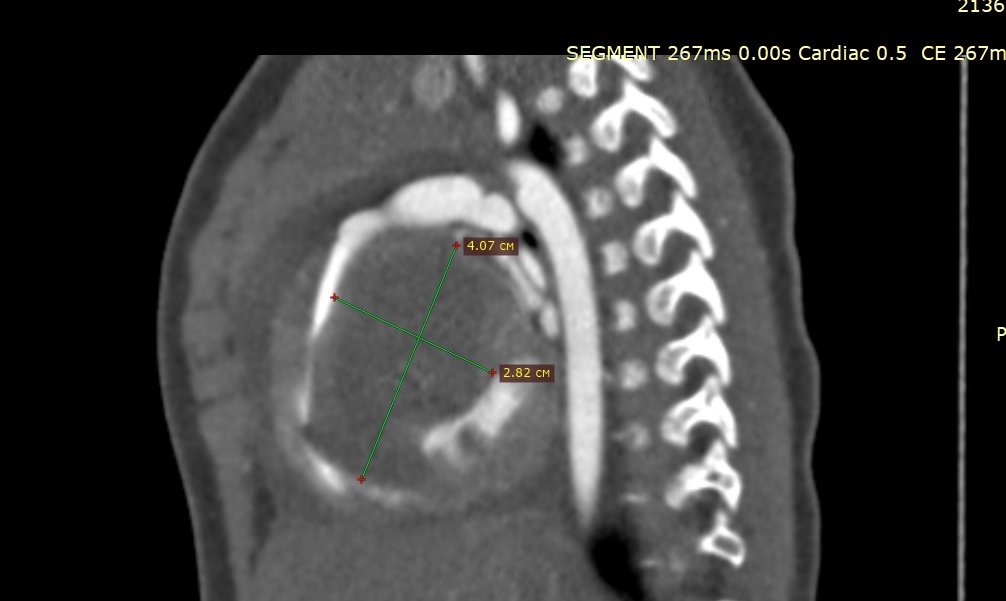

В Новосибирске кардиохирурги клиники имени Машалкина успешно извлекли из сердца младенца каменистую опухоль, занимавшую всю полость органа. Об этом сообщает пресс-служба медучреждения.

Для спасения жизни пациентки из Приморского края, у которой в возрасте трёх месяцев выявили трехкратное увеличение размеров сердца, необходимо было удалить опухоль. Врачи провели открытую операцию.